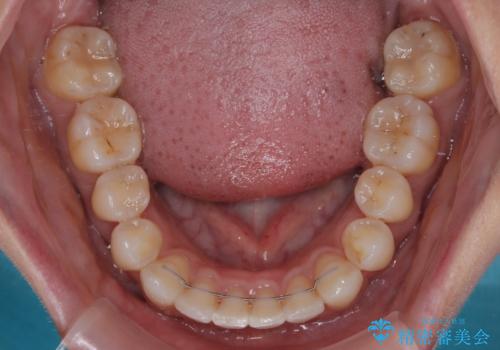

横顔は元々突出した印象ではなかったのですが、上顎前歯の角度が改善したことで、唇の閉じにくさが改善されました。